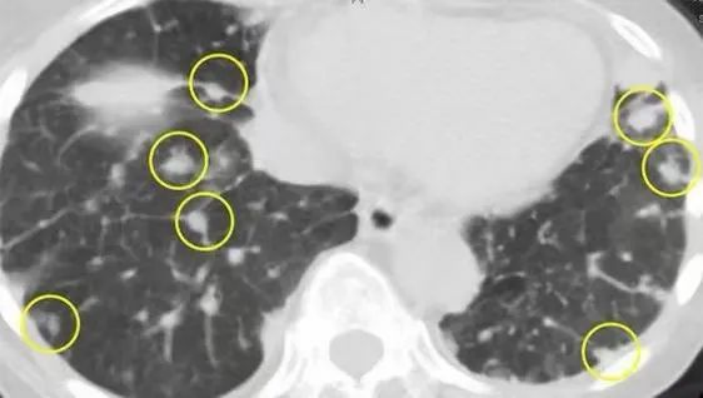

还有就是肺部“多发结节”的问题,这需要分开来看:

1)既往有肿瘤的患者:直径大于等于 10 mm 或由常规胸片检出的多发性肺结节最常由实体器官原发恶性瘤转移所致,而直径小于 5 mm 且邻近脏胸膜或叶间裂的多发性肺结节则更可能为良性病变,如肉芽肿、瘢痕或肺内淋巴结

2)如果既往无肿瘤患者,多发性肺结节的直径小于 5 mm、邻近脏胸膜或叶间裂,且为偶然检出,则更可能为良性病变,如肉芽肿、瘢痕或肺内淋巴结如果多发性肺结节的直径大于等于 10mm 或由常规胸片检出,则最可能由实体器官恶性原发瘤转移所致。